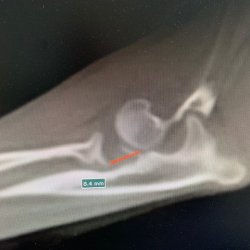

Rozárka je fenečka dovezená ze Slovenska, z romských osad. Po příjezdu do spolku Pro psí duši, z.s. kulhala na levou přední nohu, bez jakéhokoli zlepšení. Zjistilo se, že má vrozenou vadu. V lokti neměla dorostlou kost ke kloubu a nemohla se proto plně na nohu opírat. Rozárka tedy musela absolvovat náročnou a velice nákladnou operaci, bez které by nemohla nožku po celý život běžně používat.

Zjistilo se také, že tato úžasná fenečka měla rozdrcený kloub, při růstu jí jedna kost zůstala nespojena s kloubem a druhá byla moc dlouhá. Prodělala tedy nakonec operace rovnou dvě. Ačkoli se Rozárka narodila do prostředí, kde nepoznala, co je člověčí láska, nýbrž špatné zacházení, nakonec se na ní štěstí usmálo. Zamilovala se do ní jedna veterinární sestřička z Prahy. Rozárku už má u sebe doma, kde spolu rehabilitují a aplikují vodní lázně.

Průběh operace

RTG snímek končetina Rozárka